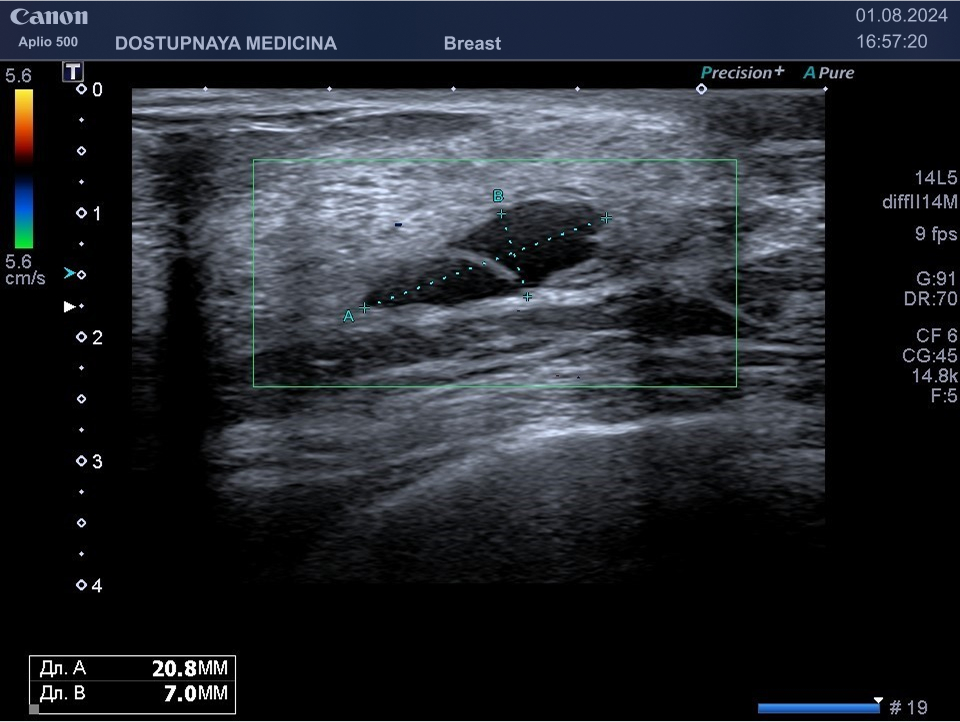

Киста может быть заполнена жидким или густым секретом. Киста с жидким секретом на УЗИ выглядит как анэхогенное (чёрное) образование округлой или овальной формы, киста с густым секретом на УЗИ выглядит как гипоэхогенное (серое) образование.